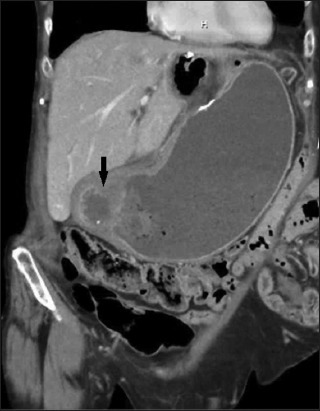

What's the Diagnosis?